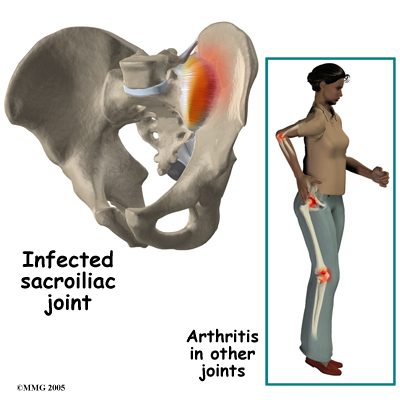

The SI joint is a synovial joint, similar to all joints such as the knee, hip and shoulder. Because of this, different types of arthritis that affect all the joints of the body will also affect the sacroiliac joint. This includes conditions such as rheumatoid arthritis, gout and psoriasis. The joint can be infected when bacteria that travel in the blood settle in the joint causing a condition called septic arthritis. This is perhaps the most worrisome cause of SI joint pain and may well require surgery to drain the infection.